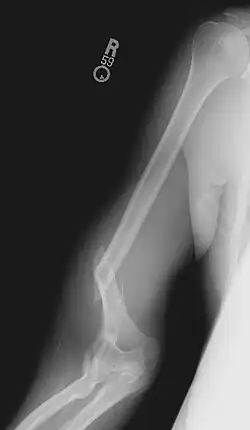

Armdrücken stellt, eine entsprechend kräftige Muskulatur vorausgesetzt, ein Risiko für Sehnen und Knochen dar, da diese der unüblichen Belastung gelegentlich nicht gewachsen sind und reißen bzw. brechen können. Durch die extrem hohen Kräfte, die beim Armdrücken entstehen können und durch die Belastung der Arme während einer Rotationsbewegung, besteht die Gefahr von komplizierten Splitter- oder Trümmerbrüchen, einhergehend mit vorübergehenden oder dauerhaften Nervenschäden.

Zudem besteht bei noch nicht gänzlich ausgebildeten Knochen die Gefahr, dass man sich die Wachstumsfuge verletzt.